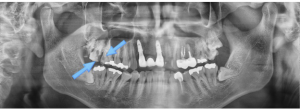

인덕원 잇몸부기와 출혈이 심한 앞니, 어떻게 치료할까

인덕원 잇몸부기와 출혈이 심한 앞니, 어떻게 치료할까     안녕하세요. 인덕원 믿음치과 원장 손동근입니다. 보철 치료의 기본은 잇몸 상태, 즉 치주 건강에 있습니다. 잇몸 관리가 얼마나...